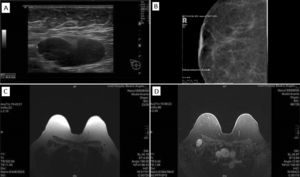

A bilateral mammogram (Fig. 1B) and a breast ultrasound were recently done in an imaging center outside the hospital, that were normal. Images were reviewed and a needle biopsy was performed (Fig. 1A). Pathological examination revealed a right axillary metastasis (Fig. 2). Immunohistochemical (IHC) results were: ER(+), CK7(+), CK20(−), RCC(−), GCDFP15(+), HER2(−), TFF1(−). Primitive breast cancer was the suspected etiology. She had recently done a colonoscopy and underwent breast MRI (Fig. 1C and D), whole body CT and bone scintigram – no other lesions were found.